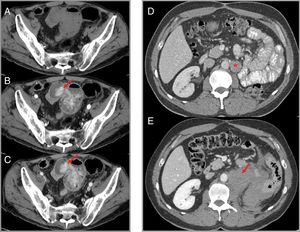

Haemorrhage: this has been described in up to 30% of patients with cancers treated with anti-VEGF drugs, with severe bleeding in 5% of cases.11 While epistaxis is the most common haemorrhagic manifestation, radiologically relevant forms are gastrointestinal bleeding (Fig. 3), intratumoral haemorrhage (Fig. 3) and haemoptysis. A meta-analysis of 23 studies analysing the risk of bleeding in patients treated with sunitinib and sorafenib shows that the risk is doubled in these patients.12

Figure 3.Haemorrhage associated with VEGF-targeted therapy. Case 1 (A–C): intestinal bleeding in a patient with metastatic renal cell carcinoma treated with sorafenib. Computed tomography (CT) shows a hyperdense area in an ileal loop in the arterial phase (B) which increases in the venous phase (C), suggestive of active bleeding (arrows). (A) Phase without intravenous contrast. Case 2 (D and E): patient with advanced renal cell carcinoma on treatment with sunitinib in whom retroperitoneal haemorrhage is detected. (D) Left para-aortic lymph node metastasis (star) can be identified. (E) A later CT scan shows retroperitoneal bleeding (arrow) originating from the metastatic lymphadenopathy.